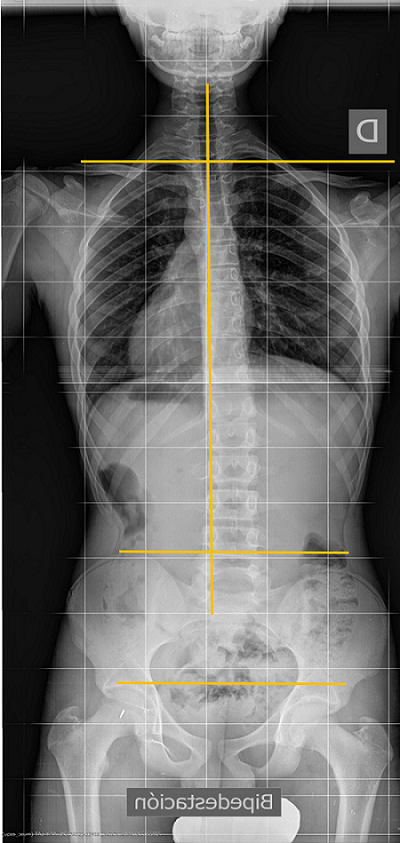

En la escoliosis, la columna vertebral en proyección frontal se verá torcida, amén de otras alteraciones secundarias a su torsión tridimensional6,7.

La escoliosis puede presentar una o varias curvas y en su evolución, no mejora (Figura 8). Por eso, se hace imprescindible su seguimiento con sucesivas telerradiografías, lo cual obliga, éticamente, a optimizar su estudio8.

Figura 8. Telerradiografía de escoliosis de una paciente a lo largo del tiempo. Mostrar/ocultar